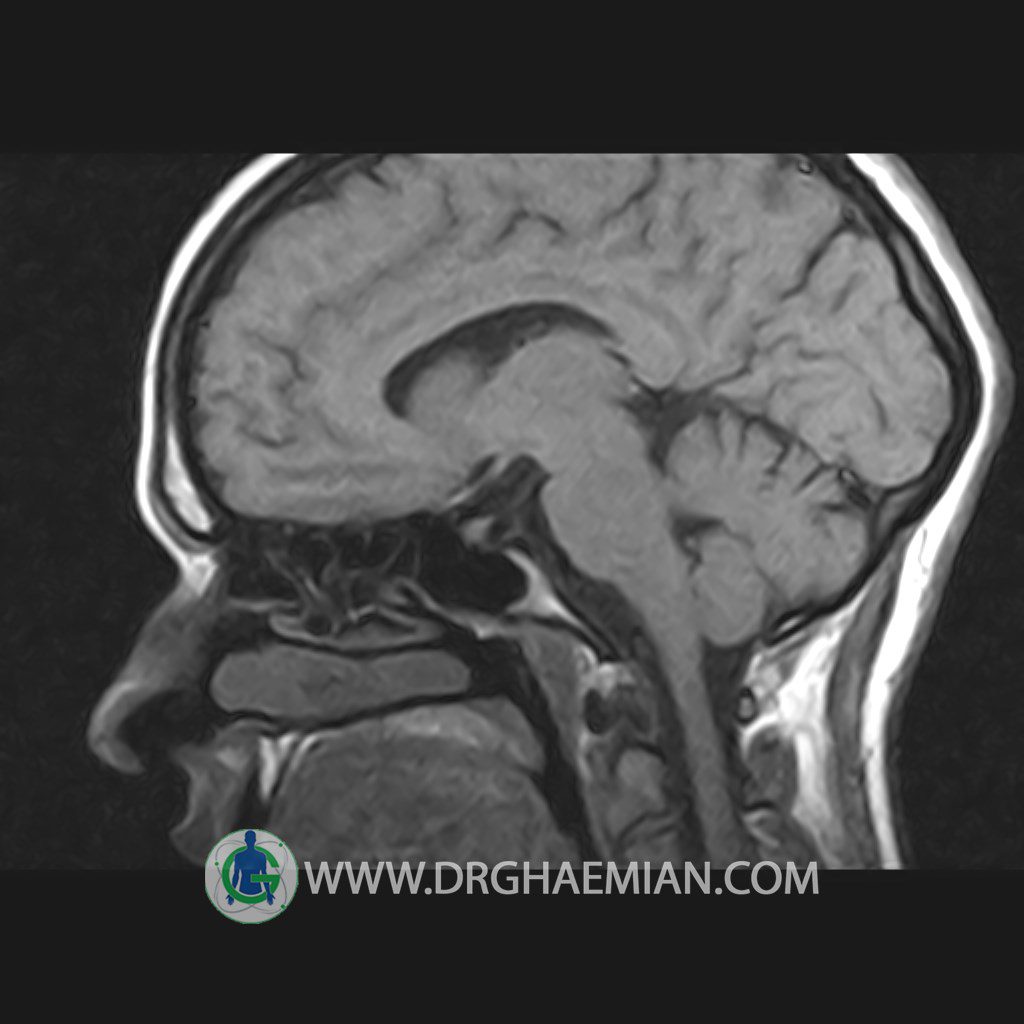

پزشکان اغلب از تصویربرداری ام آر آی برای تشخیص و درمان عارضه های پزشکی که فقط با استفاده از اشعه ایکس یا میدان مغناطیسی و امواج رادیویی قابل مشاهده است، استفاده می کنند. دستگاه ام آر آی تصاویر دقیق از ساختار های داخلی بدن ایجاد می کند. در این کیس هیپرپلازی هیپوفیز و آدنوم مشاهده می شود.

HYPOPHYSIS MRI

(with and without contrast)

Technique: Axial , coronal T1 , Axial , coronal , sagittal T2 , Axial, coronal T1 post Gd & 64 dynamic thin coronal slices.

REPORT :

The sella shows normal size , position and configuration .

The borders of its floor and walls are smooth and sharply defined .

The infundibulum is centered and of normal size .

The optic chiasm and suprasellar spaces appear normal .

The cavernous sinus and imaged portions of the internal carotid artery and carotid siphon are unremarkable .

Evaluable portions of the neurocranium show no abnormalities .

The sphenoid sinus is clear and pneumatized .

– Mild convexity at superior border of pituitary gland with post contrast homogeneous enhancement suggestive for pituitary hyperplasia & iso signal adenoma

is seen